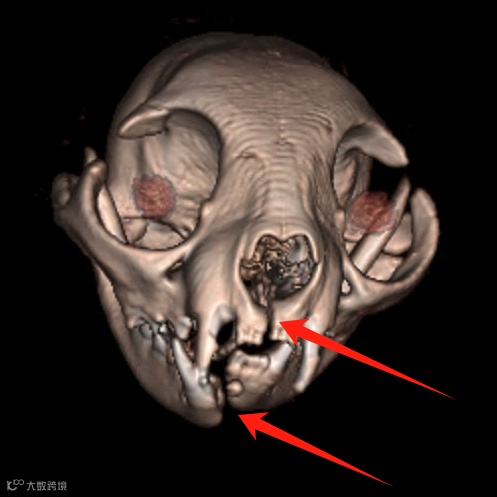

上、下颌联合骨折。